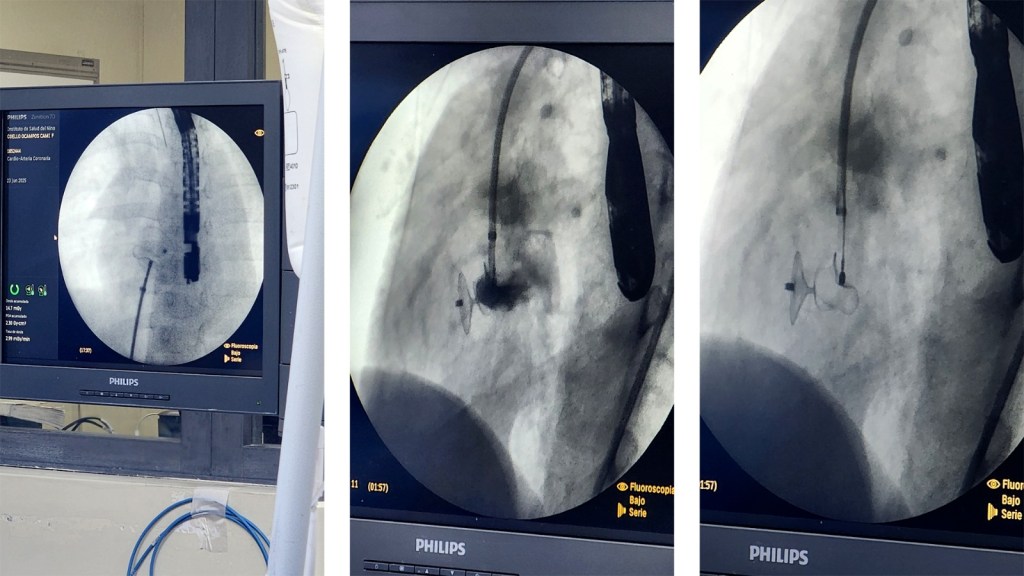

Entre el 23, 24 y 28 de junio, se realizaron 8 procedimientos bajo la dirección del Dr. Carlos Mariño (Coordinador del Servicio de Hemodinamia), el Dr. Ronald Taype y cardiólogos invitados como el Dr. Alex Catalán y el Dr. Andrés Aldazabal, junto al proctor Dr. Carlos Guerrero Maya. Los pacientes intervenidos, con edades entre 4 meses y 16 años, presentaban diferentes cardiopatías congénitas. Esta jornada también buscó sentar las bases para implementar un programa especializado en cardiopatías congénitas.

Del 25 al 27 de junio, la jornada continuó en Chiclayo bajo la coordinación del Dr. Salomón Guerrero Rodas (Jefe del Departamento de Cardiología), el Dr. William Cornelio Fuster (Coordinador del Área de Hemodinamia), los Dres. Pedro Casas y Piero Cornelio, además del valioso apoyo de un equipo multidisciplinario. Se inició con una junta médica y una ponencia sobre el uso de dispositivos para enfermedades congénitas.

Durante esta fase se realizaron 9 procedimientos exitosos en pacientes entre 3 y 54 años. Todos evolucionaron favorablemente, lo que evidenció el impacto positivo de los dispositivos Lifetech en su calidad de vida.